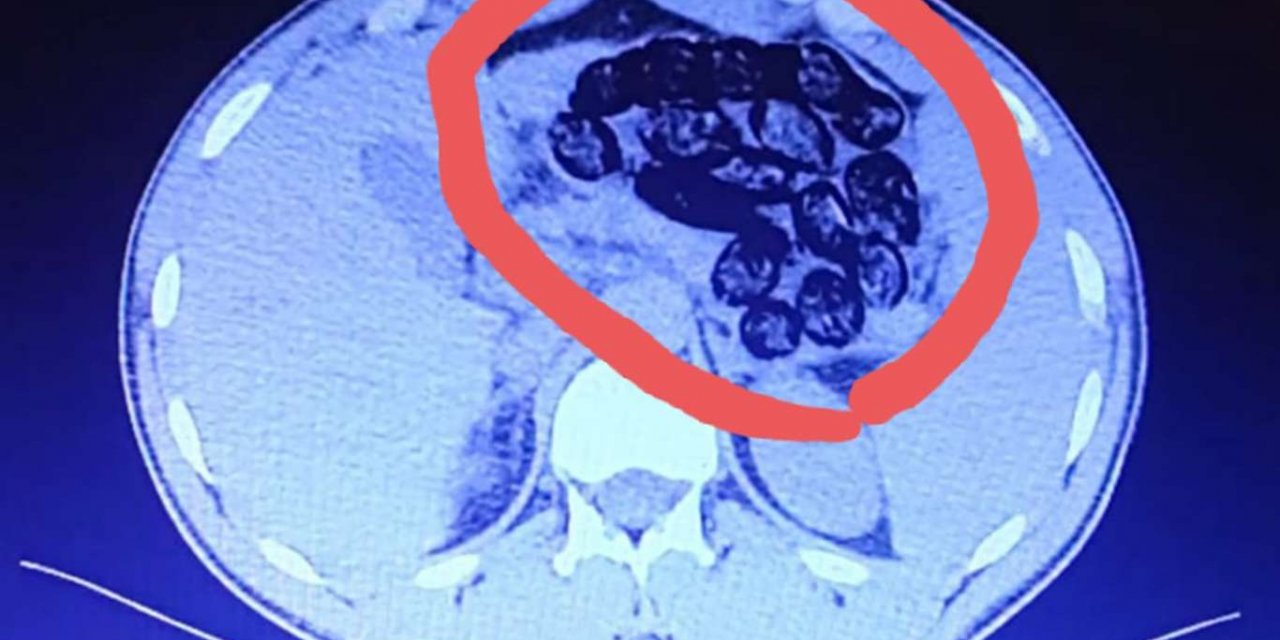

Midelerinden 920 gram uyuşturucu madde çıktı